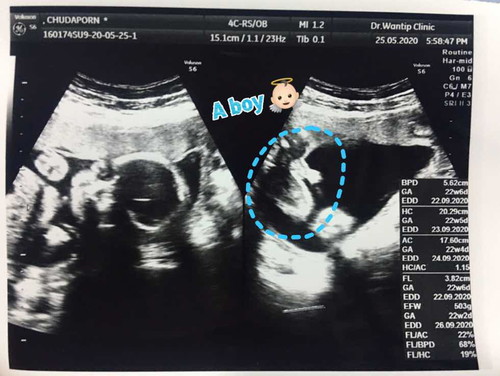

แม่ๆช่วยคอนเฟิร์มทีค่ะ เด็กชายใช่ไหมคะ😅

ต้องบอกก่อนว่าตั้งแต่ท้องมาชอบแต่งตัวเป็นพิเศษมาก มีแต่คนทักว่าได้ลูกสาว แต่หมอบอกลูกชายเริ่มสงสัยแล้วว่าตัวเองได้ลูกชายจริงไหม55555 แม่ๆช่วยคอนเฟิร์มทีค่ะ😅

ชัดเจน 🧒